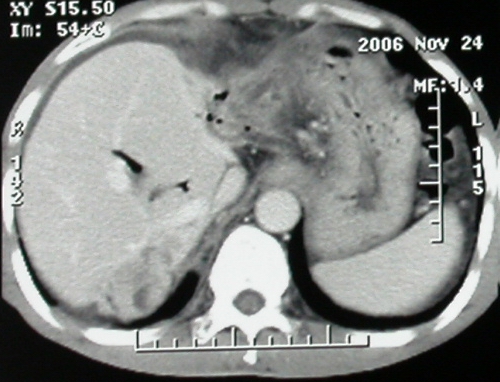

门脉主干及肠系膜上静脉近端明显增粗,尤其前者呈等低混杂密度,增强后周围见轻度环形强化。明显占位效应。肝内外胆管见大量气体影。胆囊明显增大。

考虑:1、门脉栓塞; 2、肝内外胆管积气。

ct表现:1,胰腺钩突后方肿块,不均强化,中心密度低,钩突及门静脉前移。2:肝右后叶不均强化灶,突出肝表面,3:胆囊明显增大,肝内胆管及肝总管内积气。4:腹腔内少量积液。

考虑:1:胆囊炎,胆管炎。2:肝癌合并腹腔内转移灶,腹水。